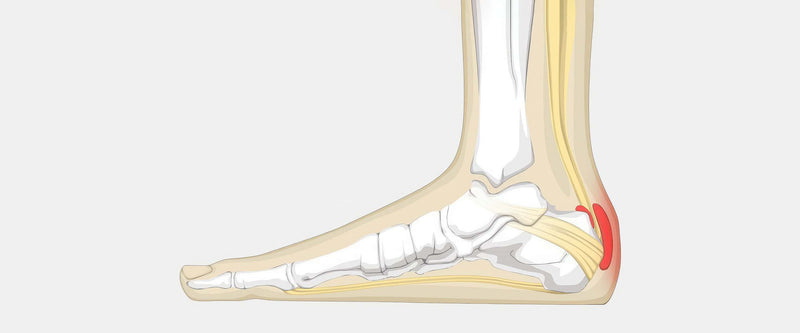

Achilles Bursitis The Complete Injury Guide Vive Health